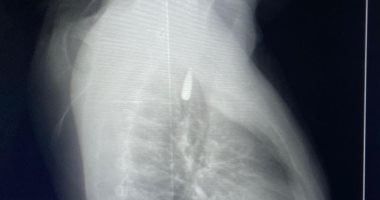

وأوضح الدكتور تامر عبد الله، عميد كلية الطب ورئيس مجلس إدارة المستشفيات الجامعية، أنه في يوم 21 أكتوبر 2025 تمكن فريق من أطباء قسم جراحة القلب والصدر والتخدير والمعاونين من إجراء جراحة دقيقة بالغة الخطورة لأحد المرضى المحجوزين من قطاع غزة، والذي كان قد تعرض لإصابة بطلق ناري في الرأس منذ فترة، استقر المقذوف على إثرها داخل تجويف القفص الصدري قرب الشريان الأورطي، وهو أكبر وأهم شرايين الجسم والمسؤول عن تغذية جميع الأعضاء الحيوية، وأضاف أن الفريق الطبي، رغم دقة الحالة وتعقيدها، نجح في استخراج المقذوف بأمان بعد عملية جراحية نادرة استمرت عدة ساعات داخل المستشفى الجامعي الجديد، حيث خضع المريض بعدها للرعاية الطبية اللازمة، وحالته حاليًا مستقرة وتحت المتابعة الدقيقة من الفريق المختص.